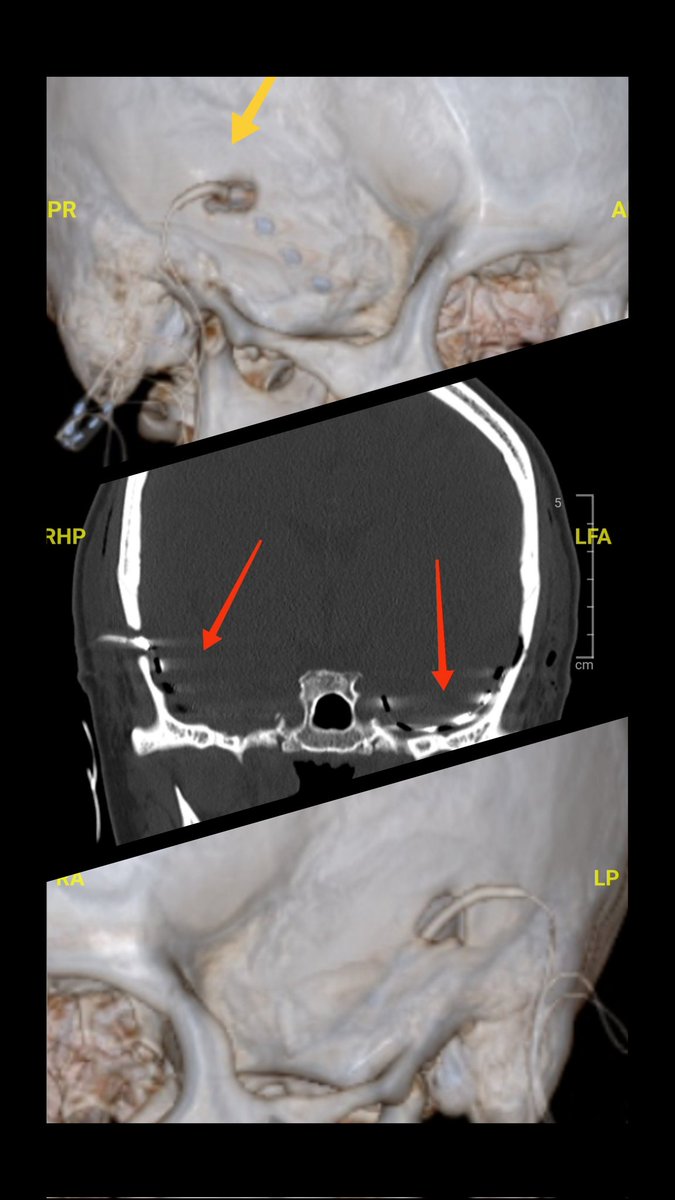

Monitoreo invasivo para epilepsia temporal bilateral refractaria. Optimizando los poquísimos recursos del sector público para pacientes vulnerables. Medicina de primer mundo para nuestros paciente fonasa. DrUribeEpilepsiaChile Ministerio de Salud Alexander Recabarren Ximena Aguilera

Monitoreo invasivo para epilepsia temporal bilateral refractaria. Optimizando los poquísimos recursos del sector público para pacientes vulnerables. Medicina de primer mundo para nuestros paciente fonasa. <a href="/UribeChile/">DrUribeEpilepsiaChile</a> <a href="/ministeriosalud/">Ministerio de Salud</a> <a href="/recabaez/">Alexander Recabarren</a> <a href="/ximenaguilera/">Ximena Aguilera</a>